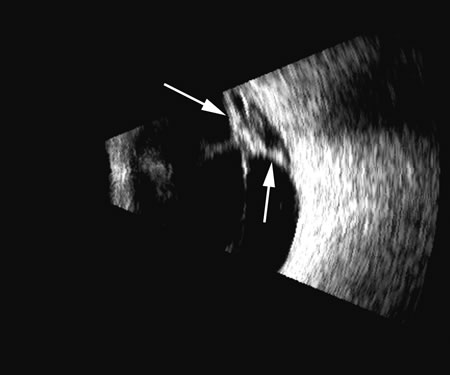

Fig. 4. A clinically well-placed posterior chamber intraocular lens nevertheless had patient complaints of photophobia and irritation due to a folded haptic (arrow).

Fig. 5. An anterior chamber intraocular lens has had the support haptics dislocate posterior to the iris plane and can be seen as typical foreign body echogenic reflections (arrows).